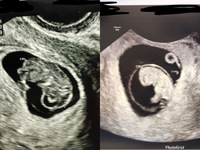

NT(nuchal translucency)とは、妊娠初期の超音波検査で見える、 胎児の首の後ろのむくみ(浮腫)のこと です。 超音波は水が溜まった部分は反射しないので、黒く抜けてみえます。 医学用語では後頚部透亮像(後頚部:nuchal、透亮像:translucency)といいます。 NT計測の規約に従って画像を拡大すると、浮腫の厚さに違いはありますが、全ての胎児に見つかりますNT NT ( nuchal translucency ) 後頚部浮腫(首の後ろのむくみ) (妊娠11週) 胎児の横顔の輪郭が出ています。 首の後ろが黒っぽく膨れています。 これをNT(後頚部の浮腫)と言います。 NTは、この部分にリンパ液が溜まった状態です。 NTは、妊娠初期に、普通の胎児でもしばしば見られることがありますが、これが厚ければ厚いほど、胎児に染色体異常がある可能性が2D・3Dのエコー写真で見る「私と赤ちゃんの実録260日」 予想外に早く破水! 「あと12時間頑張れれば4月2日よ」って、無理ですー! 何度でも産みたい! 初産でもかなえられた、痛みも恐怖もない出産 慣れない子育てに悩みながら、保育士資格の勉強をし

私のエコー写真です 妊娠初期の超音波検査で発見されるもので重要なものがこのNTです。英語ではNT(nuchal translucency)といい、胎児の首の後ろのむくみのことを言います。 写真で黒く影になっている部分です。